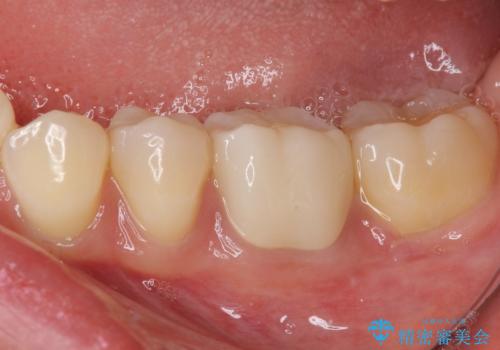

仮歯の時点で、それまでの連結クラウンから単独クラウンに変更したため、清掃性が格段に良くなりました。

オールセラミッククラウンであるため色合いはとても自然であり、また舌の感触も大変良くなり、患者様には大変満足していただきました。